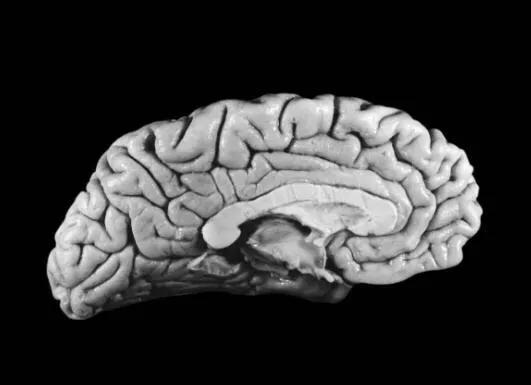

爱因斯坦去世于美国新泽西——普林斯顿。他曾在遗嘱中要求自己的尸体不要被用来进行医学检测或测试。他想被焚烧火化。但是爱因斯坦最终未能如愿,他死之后,一个科学家悄悄地偷走了他的大脑,并将他的大脑制作成大量的大脑切片用来进行医学研究与测试。

(2)科学家进一步对其大脑进行解剖研究发现,爱因斯坦的大脑比普通人的大脑少了一块儿(盖区),这样就使得他大脑左右半球的顶下叶区域非常发达,是普通人不能比的,而且他的大脑宽度约超过正常人15%,而这将会使视觉空间认知数学思维和运动想象力方面发挥着重要作用。

(3)科学研究表明,人的大脑里有约140亿个神经元细胞,普通人在整个生命过程中运用到的脑神经细胞仅有10亿个左右,仅运用了总神经细胞的10%。而爱因斯坦的脑能量较为强大,大脑里面的细胞数量多于正常人,脑神经细胞动用率甚至达到了65%。

其中利于思考的灰质层比普通人的大脑明显多很多,通常科学家们认为大脑的灰质层与人们的IQ有关。这也许就是为什么爱因斯坦智商能达到200的缘故吧……

(4)最后一个就是爱因斯坦后脑部位的枕叶区域大于正常人的20%,这使得他在科学思维过程具有较强视觉性。